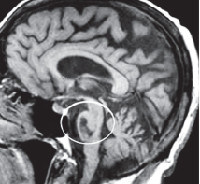

Компьютерная томография малоинформативна, поскольку определяет преимущественно неспецифические изменения церебральных структур: расширение желудочков и субарахноидальных пространств. Специфичным признаком, регистрируемым при помощи КТ головного мозга, является уменьшение толщины передней мозжечковой ножки. Более полно диагностировать оливопонтоцеребеллярные дегенерации позволяет МРТ головного мозга. С ее помощью можно визуализировать атрофические изменения в мосте и продолговатом мозге. Для определения типа наследования патологии необходима консультация генетика и генеалогическое исследование. При подозрении на ОПЦД I или II типов возможна ДНК-диагностика. Пациенты с нарушением зрения нуждаются в консультации офтальмолога.